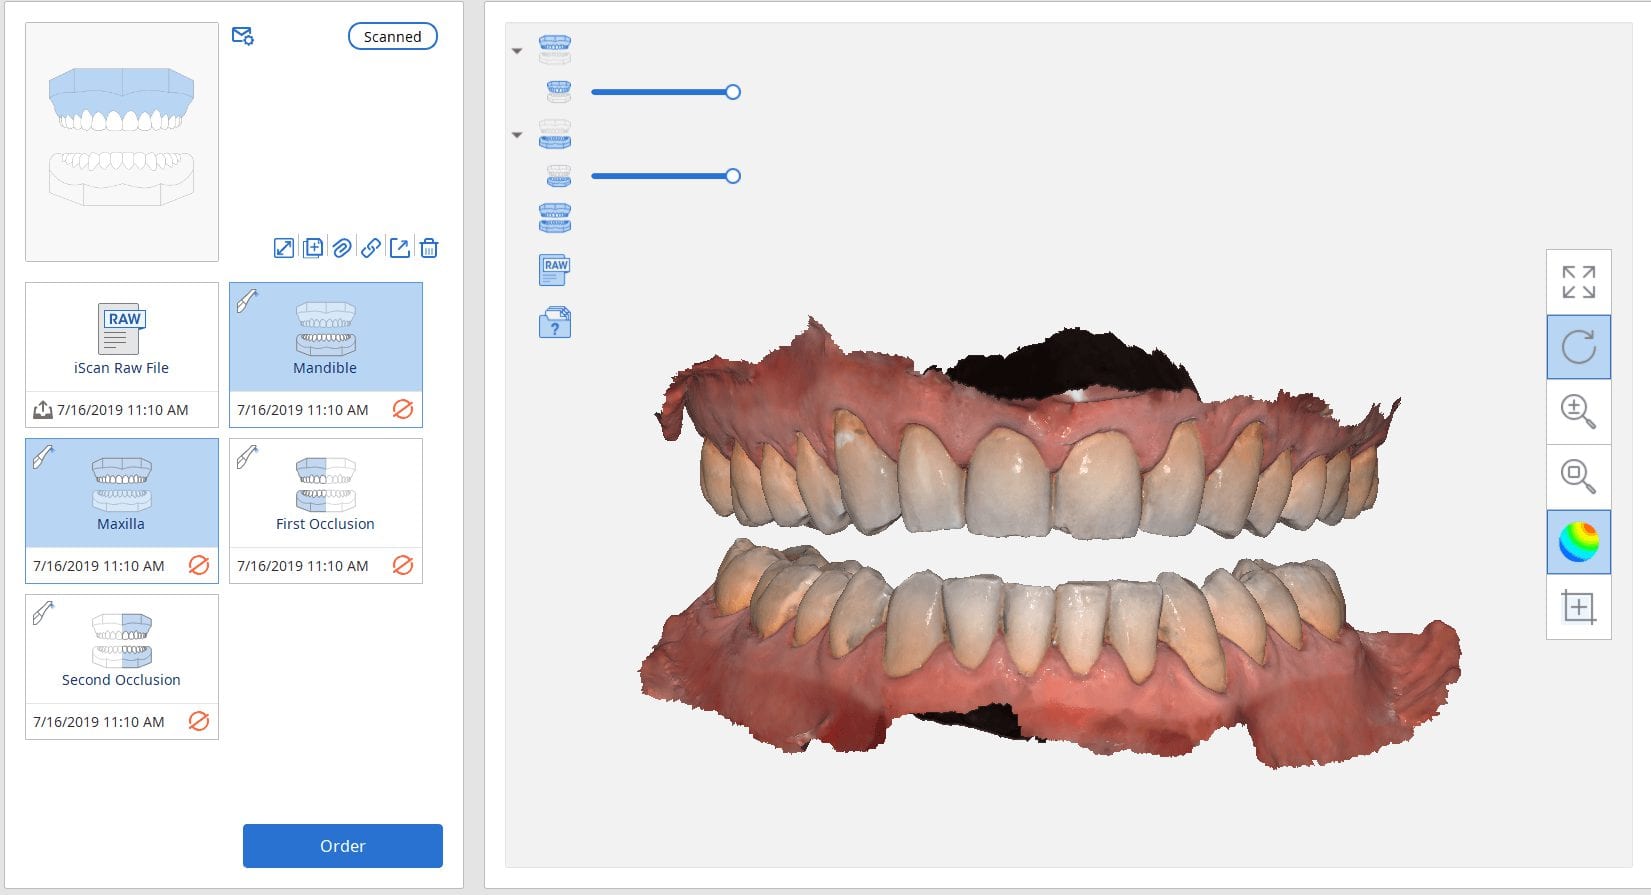

July 18, 2019There are multiple ways one can capture the bite for a patient. In this clinical case, we focus on the easiest way to capture two bites (one in maximum intercuspation […]